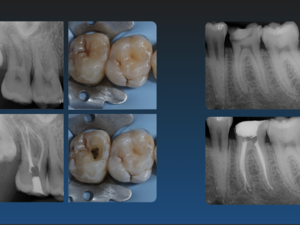

Endodontiste

Collaboration en Endodontie Exclusive – Spécialiste Itinérant (Secteur Haute-Savoie / Chamonix)

Collaboration En Endodontie Excl...